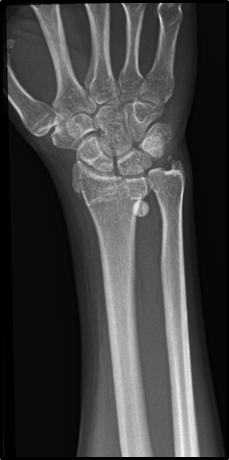

This is a 41-year-old male patient, provided his written informed consent, from and resident of Minatitlán, Veracruz with a history of apparent good health, who was transferred by Red Cross paramedics on July 05, 2019 to the Emergency Department, after suffering a fall from a height of 4 meters in his work area. The diagnosis of polyconcussion was established and the evaluation of cabinet studies identified: distal metaphyseal fracture of the right radius and ulna, intertroncantal fracture of the left femur and costal fractures from the second to the seventh right costal arch; at this time, he was diagnosed as polytrauma/unstable thorax (Figure 1–3).

Figure 1 Rx of Thorax AP. Multiple fracture strokes are observed in 2nd, 3rd, 4th, 5th, 6th and 7th right rib arches. No lung involvement.